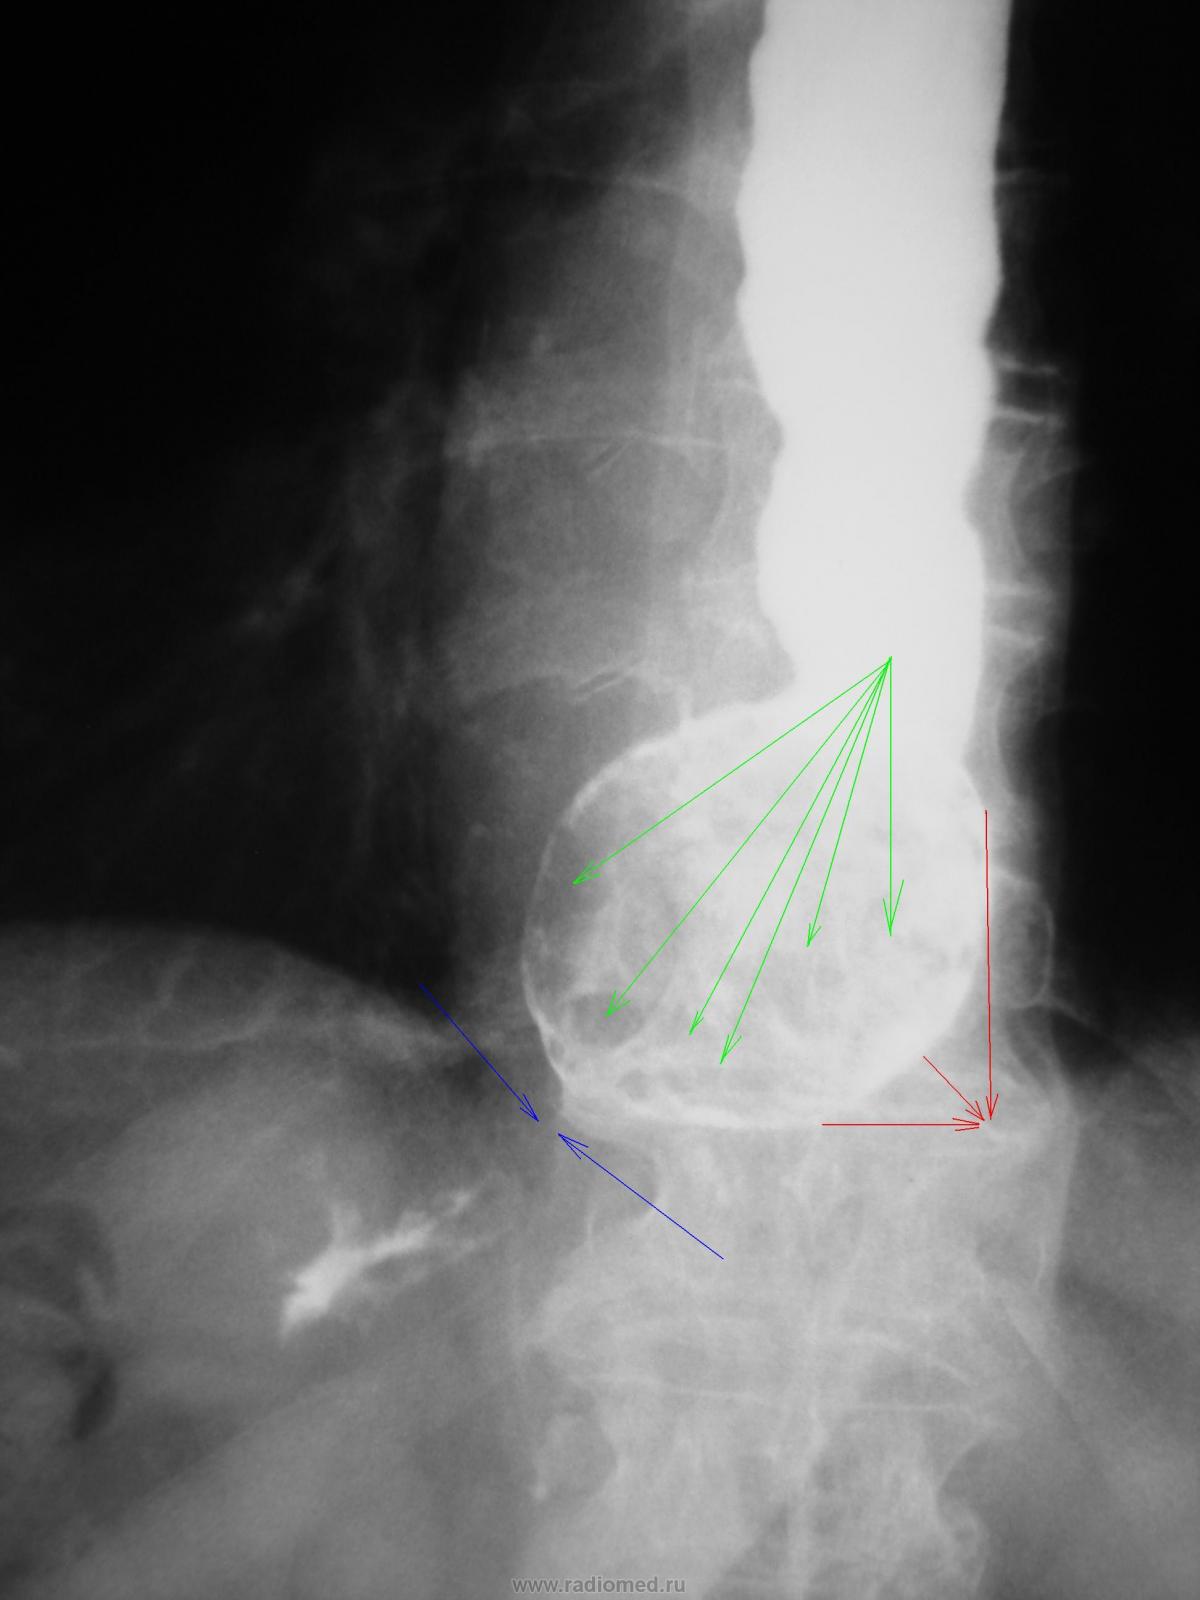

Все становится понятным. В результате инволютивных изменений, наступило "возрастное" снижение тонуса диафрагмы, вторично расширилось пищеводное отверстие диафрагмы, образовалась грыжа пищеводного отверстия диафрагмы, с пролабированием довольно значительной части желудка в грудную полость - желтые стрелки, в которой, а дистальной части её (грыжи) скапливалось значительное количество механически недостаточно размельченной пищи - красные стрелки.

По всей видимости, в результате переполнения этого грыжевого мешка "пищевым шанкром" и пищеварительными "соками", в ортоположении происходило "заваливание" переполненной грыжи на диафрагму - красные стрелки. Скопившиеся в ней (грыже) пищеварительные массы - зеленые стрелки способствовали еще большему переполнению - "заваливанию", создавая, как следствие, формирование некоторого "перегиба" - синие стрелки, что безусловно препятствовало, при всех вышеперечисленных факторах продвижению контраста дистально.

Следовательно, НИ О КАКОМ ШТОПОРООБРАЗНОМ ПИЩЕВОДЕ, ДИвЕРТИКУЛАХ ПИЩЕВОДА, НЕВРОЗЕ ПИЩЕВОДА ГОВОРИТЬ НЕ ПРИХОДИТСЯ. В результате пролабирования части желудка в грудную полость возникло " искусственное удлинение" пищеварительной трубки в грудной полости - пищевод + часть желудка. Возт пищевод и вынужден был "собраться в гармошку". А с учетом инволютивного снижения тонуса пищеварительной трубки - вот и компонента расширения просвета его. А если, учесть постоянное "забивание" пищевыми массами, то и хроническое приспособительное расширение пищевода вполне объяснимо.